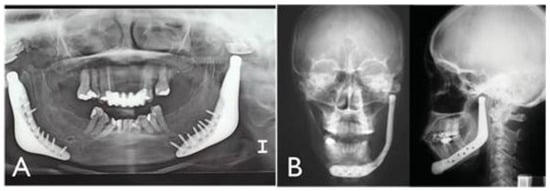

Figure 4. (A) Postoperative panoramic radiograph showing bilateral custom temporomandibular joint (TMJ) prosthesis by TMJ Concepts, Inc. (Ventura, CA). (B) Postoperative posteroanterior radiograph showing unilateral custom TMJ prosthesis by TMJ Concepts, Inc.